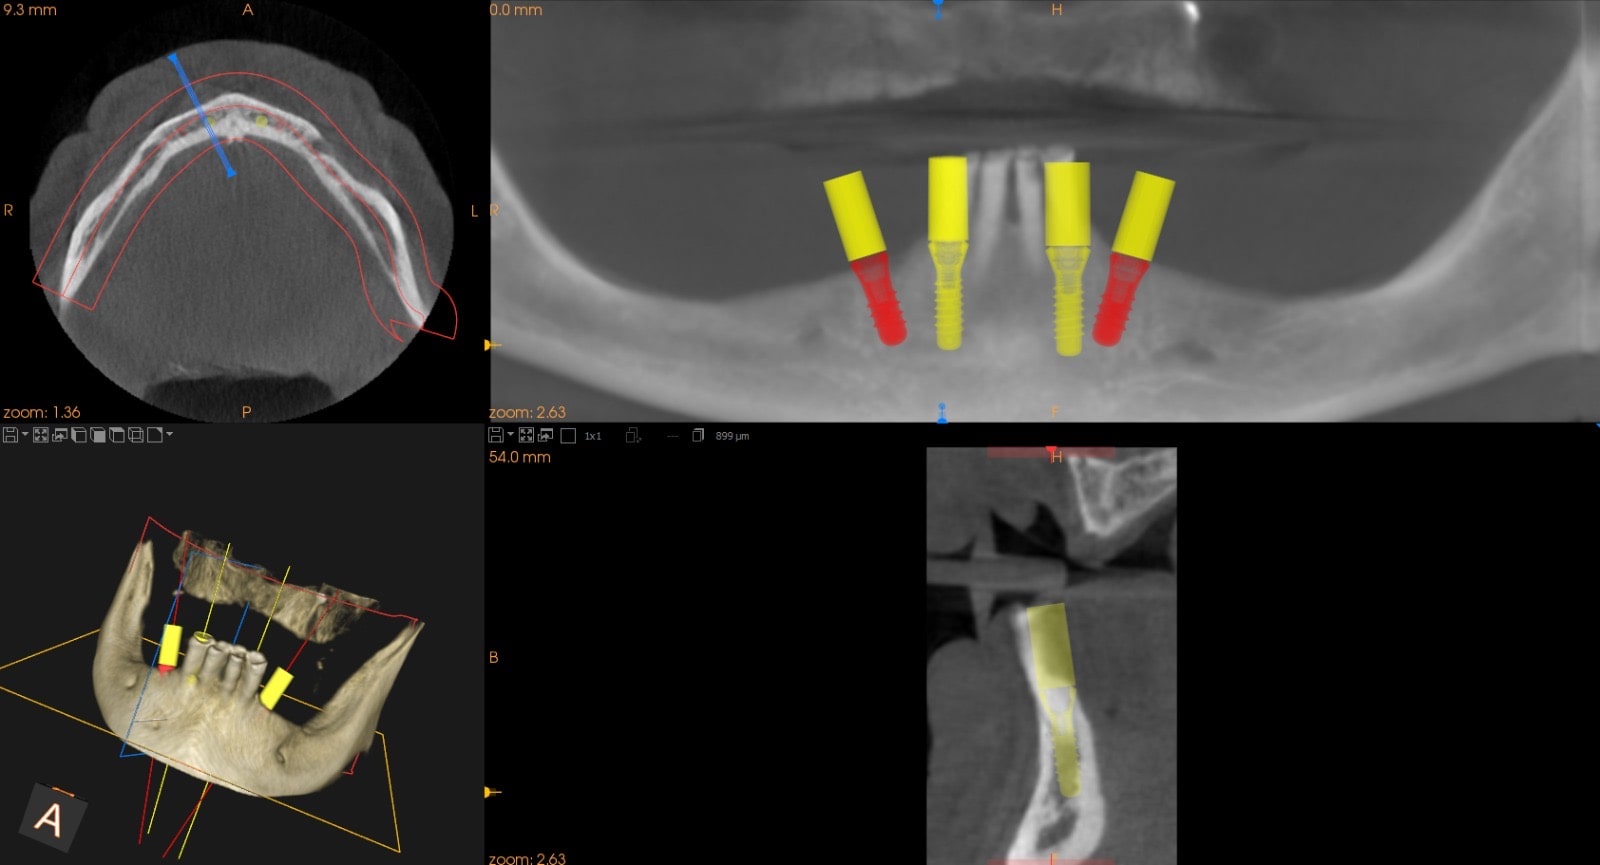

TAC Cone Beam 3D (CBCT)

Per i casi più complessi o per la pianificazione implantare e chirurgica, ci avvaliamo della tomografia computerizzata Cone Beam 3D.

Questa tecnologia ci consente di ottenere una visione tridimensionale dell’osso, dei denti e delle strutture anatomiche circostanti, permettendoci di:

• Valutare in modo dettagliato la qualità e quantità di osso disponibile.

• Individuare eventuali lesioni, granulomi o anomalie anatomiche.

• Programmare interventi con maggiore sicurezza e predicibilità.

• Mostrare al paziente immagini chiare per una migliore comprensione del trattamento.

L’esperienza diagnostica risulta così più affidabile e trasparente, per il medico e per il paziente.